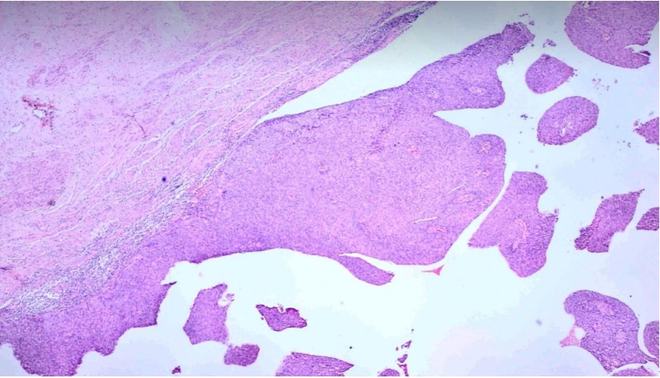

1、宫颈活检首先会先做阴道镜的检查,在病变可疑的地方,或者同时在3点、6点、9点和12点的地方取下活检,但是所取到的宫颈组织都是很小的,基本都是和豆粒那么大一样,而且患者不会感觉到小小疼痛,流血也不是特别的多,在手术以后只要压迫纱布止血就可以了。